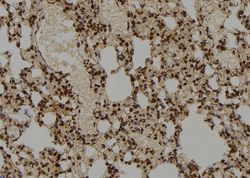

Supportive validation

- Submitted by

- LSBio (provider)

- Main image

- Experimental details

- 1:100 staining rat lung tissue by IHC-P. The sample was formaldehyde fixed and a heat mediated antigen retrieval step in citrate buffer was performed. The sample was then blocked and incubated with the antibody for 1.5 hours at 22°C. An HRP conjugated goat anti-rabbit antibody was used as the secondary.